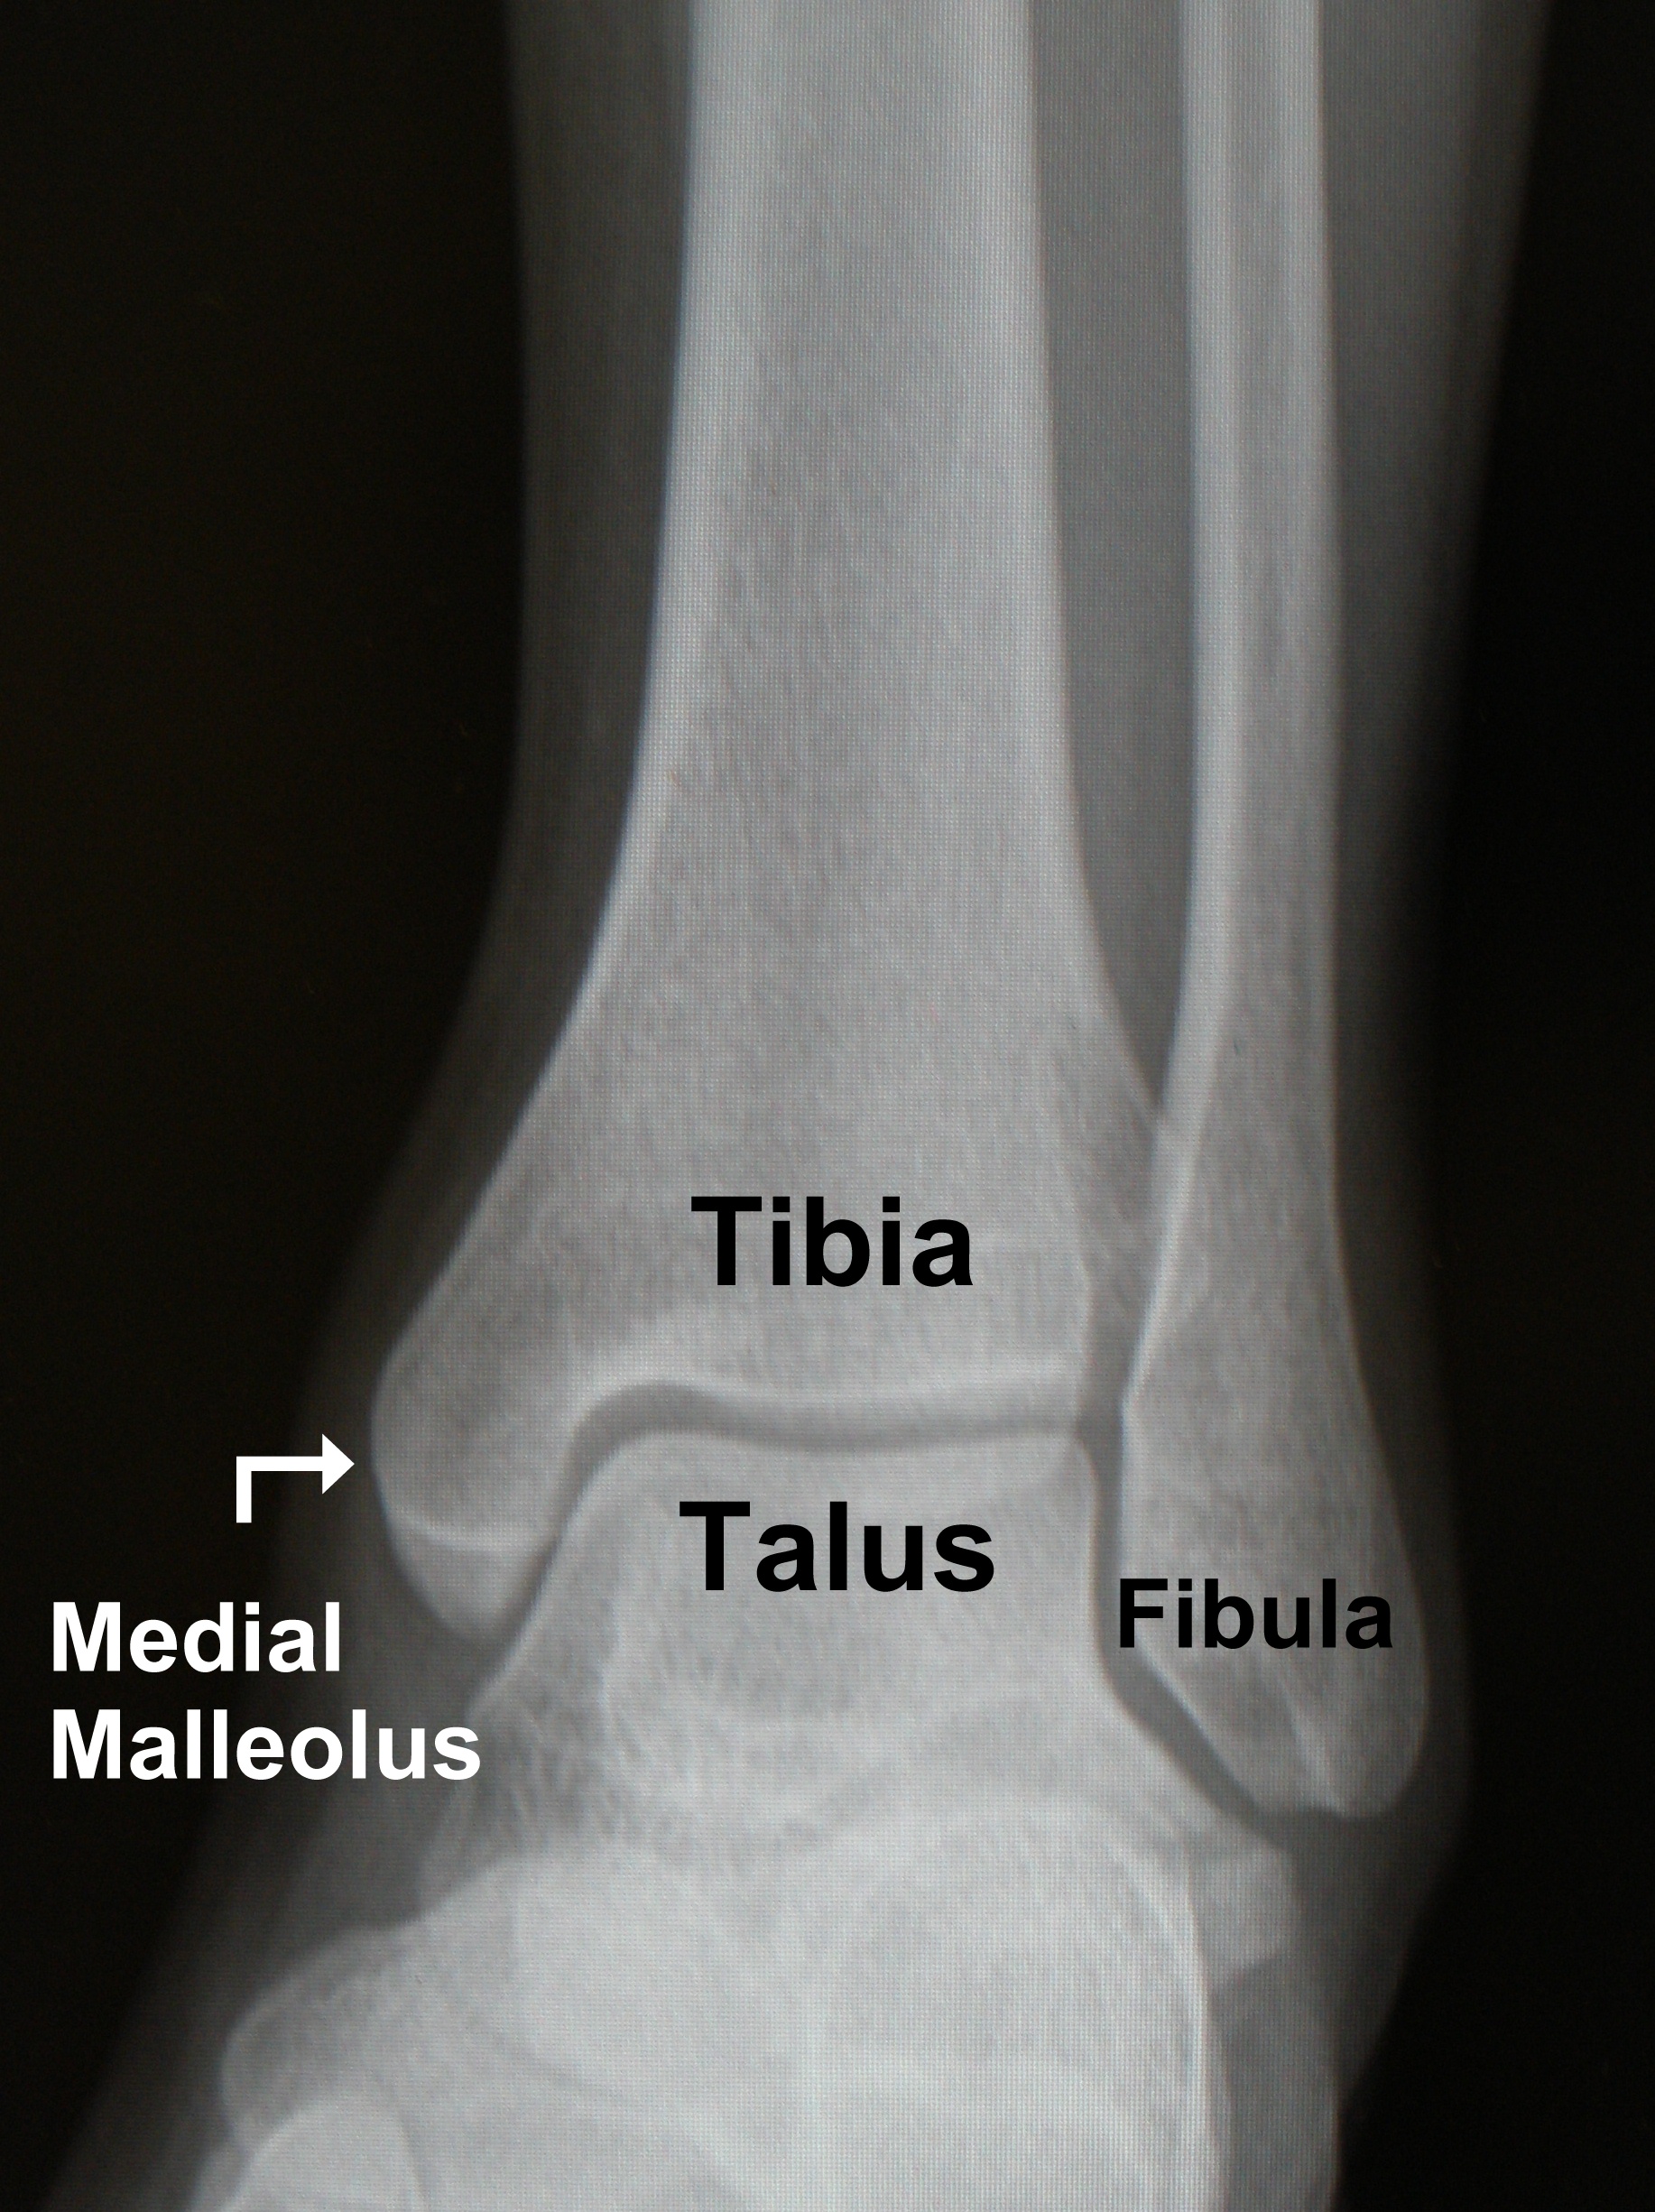

Fractured ankle How to treat them and how to recover from them The